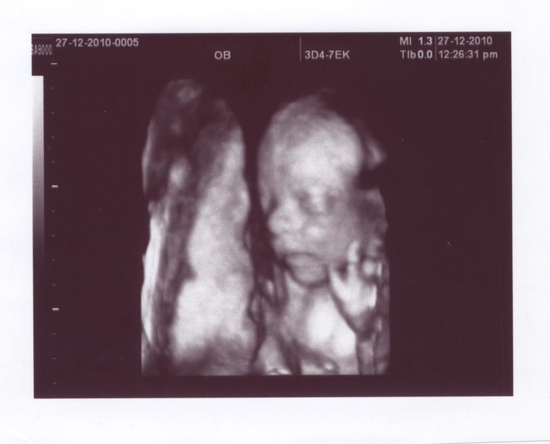

Вот и пришёл второй прилив сил, которого я так ждала. Через 2 дня нам уже 22 недели. Завтра делаем первый скрининг. По плану он должен быть вторым, но к большому сожалению первый скрининг пришлось пропустить. Лежала в больнице под капельницами. За время ...